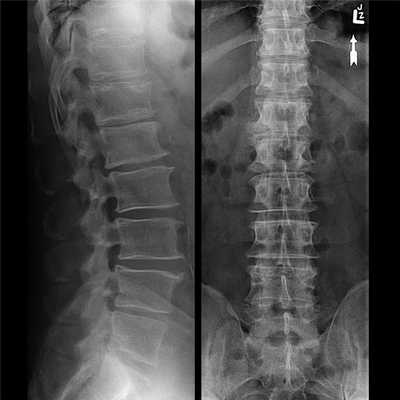

- рентгенография. Наиболее информативна при шейно-грудном остеохондрозе. На полученных изображениях заметны деформированные позвонки, уменьшение промежутков между ними, образовавшиеся костные наросты;

- обзорная двухпроекционная рентгенограмма позвоночника